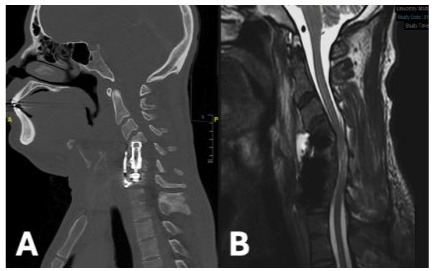

42-year-old man with past medical history significant for intravenous drug use (IVDU), untreated Hepatitis C (HCV), endocarditis and retropharyngeal abscess returned to the hospital with a chief complaint of right upper extremity (RUE) weakness and dysphagia. Past surgical history includes C5-C6 ACCF one month prior for MRSA osteomyelitis and associated spinal epidural abscess, after which the patient left against medical advice (AMA) before posterior fixation could be performed. CT Cervical Spine discovered cervical kyphosis and cage subsidence (Figure 3A). MRI Cervical Spine confirmed severe canal stenosis as well as a prevertebral abscess (Figure 3B). The patient was placed in cervical traction using Gardner-Wells tongs, which improved the cervical deformity. His RUE weakness, consisting of 3/5 deltoid and 4/5 bicep strength, was persistent despite improvement in alignment. On HD3, an anterior corpectomy revision was planned, however, only a washout was performed due to extensive infection burden and frank purulence. The patient was then positioned prone and a posterior cervicothoracic fusion from C3-T2 was completed. On HD14, once medically cleared, the patient returned to the operating room and a C3-C6 ACCF using an expandable titanium cage (Figure 4). Two-weeks following surgery the patient regained full strength throughout except 4/5 strength in right deltoid. Unfortunately, the patient again left AMA.

Figure 3: Sagittal CT Cervical Spine without Contrast (A) and T2 MRI Cervical Spine without Contrast (B) demonstrating subsidence of anterior hardware and cervical kyphosis causing severe canal stenosis and cord compression.

Figure 4: Post-operative sagittal CT Cervical Spine without Contrast showing improved alignment and anterior hardware (A). Sagittal T2 MRI Cervical Spine without Contrast confirming patent canal with relief of cord compression (B).